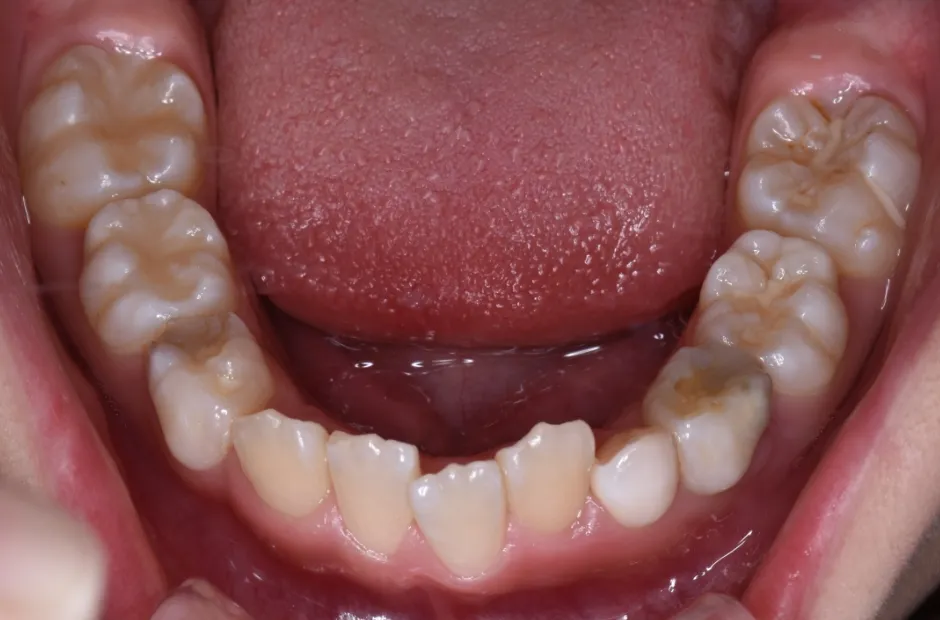

拡大床装置

叢生

| 診断名・主訴 | 叢生 |

|---|---|

| 年齢・性別 | 10歳・女性 |

| 治療期間・回数 | 2年半 |

| 治療に用いた主な装置 | 拡大床装置 |

| 抜歯部位 | なし |

| 治療費 | 30万円(税抜) |

| リスク・副作用 | 装置による違和感・疼痛・歯肉退縮・歯根吸収・虫歯のリスクなど |

治療前

治療中

治療後